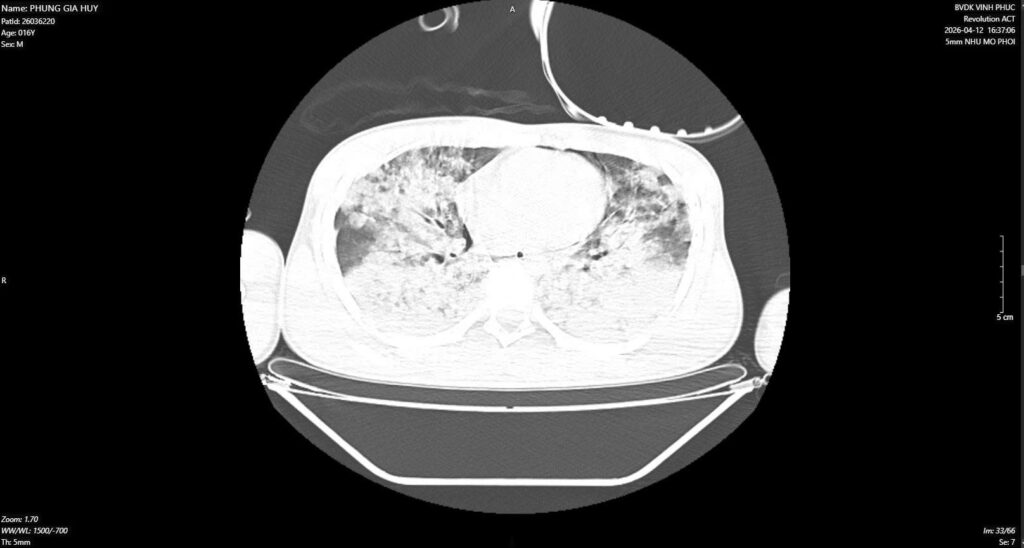

Phim chụp cho thấy phổi của người bệnh bị tổn thương nặng

Khi nhập viện, tình trạng người bệnh rất nguy kịch: hôn mê sâu, phụ thuộc hoàn toàn vào máy thở, đồng thời xuất hiện hội chứng suy hô hấp cấp tiến triển (ARDS) ở mức độ nghiêm trọng, với chỉ số P/F (thước đo khả năng trao đổi oxy của phổi0 giảm xuống dưới 60. Bên cạnh đó, người bệnh liên tục xuất hiện các đợt phù phổi cấp, khiến tình trạng thiếu oxy trong máu ngày càng trầm trọng.